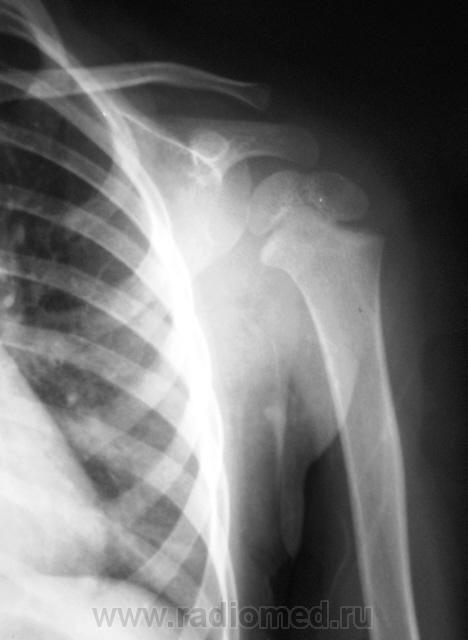

Пол пациента: Мужской пол Тип патологии: Травма Область исследования: Скелетно-мышечная система Методы исследования: Rg Ребенок доставлен по «ургенту». Травма. Направлен на рентгенографию левого плечевого сустава. https://radiomed.ru/sites/default/files/styles/case_slider_image/public/user/12/2.p1190014a.jpg?itok=1gdJVd7R https://radiomed.ru/sites/default/files/styles/case_slider_image/public/user/12/3.p1190015.jpg?itok=J2sCFP2r https://radiomed.ru/sites/default/files/styles/case_slider_image/public/user/12/4.p1190015a.jpg?itok=J9XWCaEU ID:11399 Ср, 19/01/2011 - 17:41 #1 Катенёв Валенти... Не на сайте Был на сайте: 7 лет 2 недели назад Зарегистрирован: 22.03.2008 - 22:15 Публикации: 54876 Для сравнения, дежурный хирург, попросил сделать правый плечевой сустав.Приложения: Ср, 19/01/2011 - 18:50 #2 Vega Не на сайте Был на сайте: 3 месяцев 1 неделя назад Зарегистрирован: 22.01.2009 - 19:16 Публикации: 1087 Перелом левой ключицы Ср, 19/01/2011 - 19:22 #3 Ola-la Не на сайте Был на сайте: 10 месяцев 6 дней назад Зарегистрирован: 06.12.2008 - 09:33 Публикации: 1786 Может быть, если есть клиника, но немного сомнительно. А почему опять нет второй проекции? https://www.instagram.com/pediatricradiology/ Ср, 19/01/2011 - 20:11 #4 Катенёв Валенти... Не на сайте Был на сайте: 7 лет 2 недели назад Зарегистрирован: 22.03.2008 - 22:15 Публикации: 54876 Ola-la wrote: Может быть, если есть клиника, но немного сомнительно. А почему опять нет второй проекции? Ургент! Как дежурный врач требует, так лаборант и делает. Ср, 19/01/2011 - 21:25 #5 Ola-la Не на сайте Был на сайте: 10 месяцев 6 дней назад Зарегистрирован: 06.12.2008 - 09:33 Публикации: 1786 А у нас дежурные требуют всегда в двух проекциях. https://www.instagram.com/pediatricradiology/ Ср, 19/01/2011 - 21:54 #6 Катенёв Валенти... Не на сайте Был на сайте: 7 лет 2 недели назад Зарегистрирован: 22.03.2008 - 22:15 Публикации: 54876 Ola-la wrote: А у нас дежурные требуют всегда в двух проекциях. Сравнили! У Вас, кто дежурит? А, у нас кто? Ваши, что-то хоть сделают, а наши в основном наблюдают...с определенного расстояния.

Для сравнения, дежурный хирург, попросил сделать правый плечевой сустав.

Перелом левой ключицы

Может быть, если есть клиника, но немного сомнительно. А почему опять нет второй проекции?